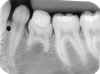

ANOMALIAS

1